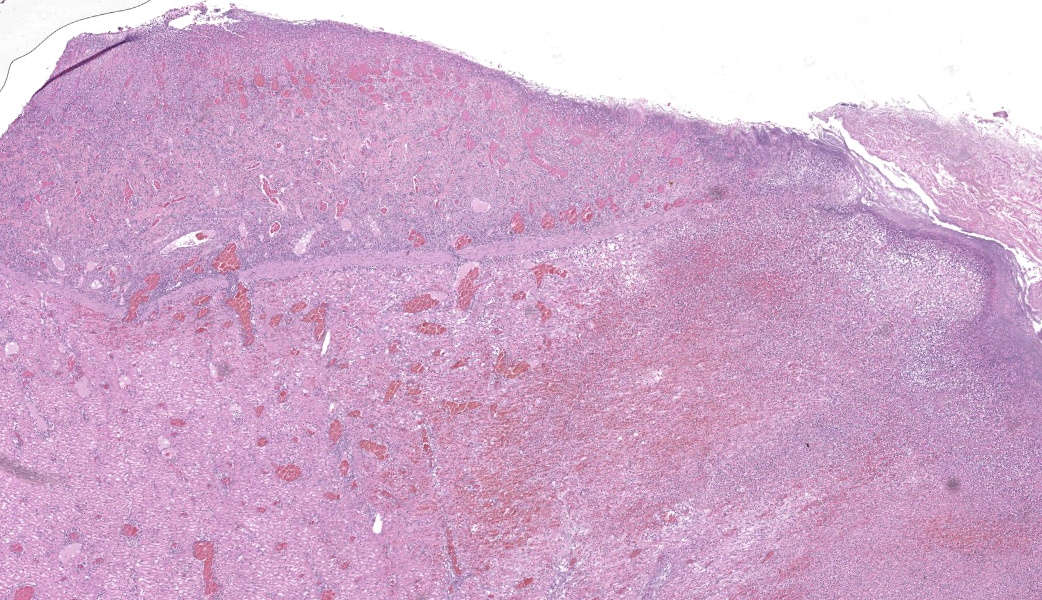

Findings are very similar in all cases that were submitted to the diagnostic laboratory.In all samples from the grossly discolored and swollen segment there was transmural necrosis of the intestine with extensive hemorrhage extending into the mesenteric fat. In the adjacent viable intestine there was eosinophilic infiltration of variable intensity. There was multifocal necrosis of mesenteric fat and, in some sections, diffuse eosinophilic infiltration. Large vessels were dilated and many contained thrombi.

Acute transmural necrotizing eosinophilic enteritis and eosinophilic peritonitis with arterial mesenteric thrombi and rare intralesional nematode larvae (spirurid)Contributor's Comment:

- Small intestine: Enteritis and peritonitis, necrotizing and eosinophilic, chronic, regionally extensive, severe.

The JPC’s own MAJ Katie Scott moderated Conference 6 and took participants on a journey of cases from around the world; each one was from somewhere outside of the continental U.S., highlighting the truly global nature of the WSC and the importance of international contributions to pathology education. This first case provided an excellent opportunity to review of the pathogenesis and life cycle of Spirocerca lupi, both of which are well-covered in the contributor’s comment. Additionally, the lesions of spirocercosis that are considered pathognomonic in the dog were covered and include aortic scarring with aneurysms, thoracic spondylitis, and caudal esophageal nodules. Special attention was paid to the chronic arterial thrombi present in numerous arteries in this case, which are a classic part of the pathogenesis of this parasite due to its arterial migratory routes and chronic intimal irritation. Participants were also reminded of the importance of specifying what type of vessels (arteries, arterioles, veins, lymphatics, etc.) are affected when giving a description, as this can provide important clues towards pathogenesis of some diseases that may preferentially affect a specific vessel type.Spirocerca lupi is one of a handful of helminths that are classified as Group I carcinogens by the International Agency for Research on Cancer (IARC) due to the well-documented malignant transformation of S. lupi esophageal nodules into esophageal fibrosarcomas or osteosarcomas in up to 25% of infected dogs.6 Less commonly, chondrosarcomas or undifferentiated pleomorphic sarcomas can also be seen.6 Metastasis to multiple locations throughout the body, including the lungs, kidneys, stomach, spleen, heart, and tongue, occurs frequently.6,7 Significantly higher levels of interleukin-8 (IL-8) have been documented in dogs with malignant esophageal nodules.4 IL-8 is released by activated fibroblasts in pre-neoplastic nodules and is chemotactic for neutrophils. IL-8 is also involved in the tumor progression of human herpesvirus-4 (Epstein–Barr virus)-induced carcinomas.4